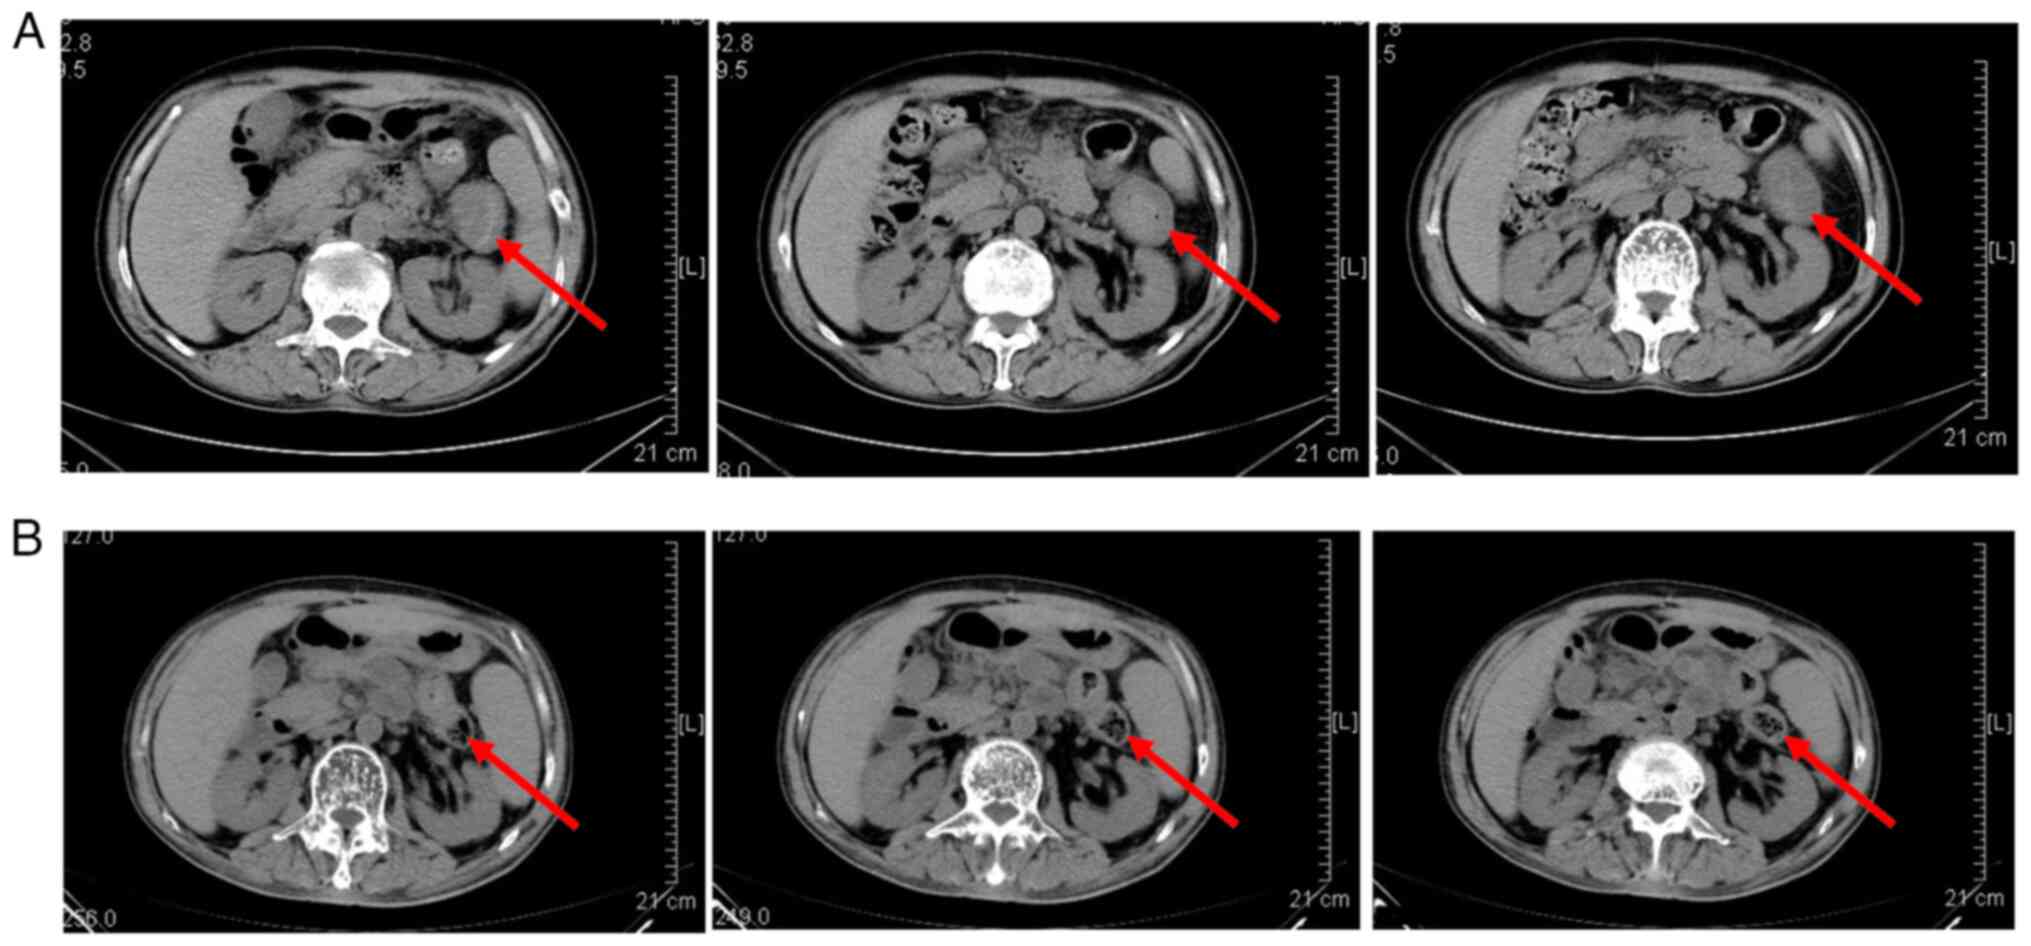

Among the 10 patients, one patient succumbed 24 days after the infusion of CAR-T cells due to rapidly progressing disease caused by heavy tumor burden. The direct cause of death was pneumonia and gastrointestinal bleeding and the treatment efficacy could not be evaluated. The remaining nine RRMM patients did not receive any treatment for MM after infusion of CAR-T cells and were followed up regularly. The overall response rate (ORR) of nine patients was 88.9%, with eight (88.9%) patients achieving partial remission (PR) or above. Among them, seven (77.8%) patients achieved complete remission (CR) with negative MRD, one (11.1%) patient achieved PR and one (11.1%) patient had stable condition (SD; Table II). The median follow-up time of nine patients were 337 (253-504) days, with a median time to response of 43 (22-169) days, and a median PFS of 337 (253-504) days. Among the eight patients who achieved PR or above, the duration of disease control exceeded six months, and three of them maintained disease remission state for more than a year. The infusion dose of CAR-T cells in one SD patient was 0.5x106/kg. At present, among the nine patients, only one patient with SD experienced disease progression 337 days after receiving CAR-T infusion, while the disease status of the remaining patients remained stable at a median follow-up time of 337 (253-504) days. Among the three patients with extramedullary involvement, two patients had disappearance of extramedullary lesions and one patient had a stable disease status (Fig. 1).

Figure 1

Response of extramedullary invasion. (A) A patient presented with colon plasmacytoma. The tumor enlarged gradually and lasted for nearly half a year although he had been treated with two lines of anti-MM drugs. (B) After the anti-BCMA CAR-T cell immunotherapy for one month, the extramedullary lesion completely disappeared. The arrows indicate the colon plasmacytoma. BCMA, B-cell maturation antigen; CAR-T, chimeric antigen receptor T.